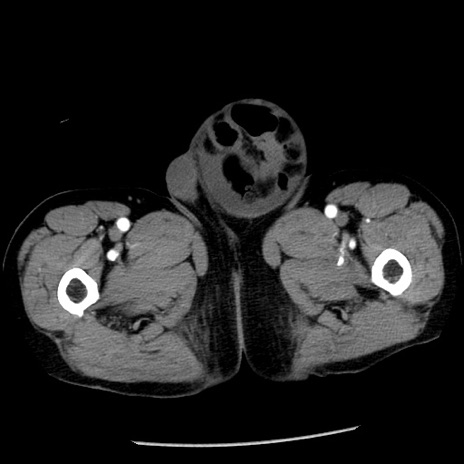

症例26(横断像)

【症例】80歳代男性

【主訴】嘔吐

【現病歴】昨晩2回嘔吐あり、今朝になっても嘔吐あり。来院。

【既往歴】胃潰瘍

【身体所見】意識清明、BT 37.6℃、BP 166/95mmHg、HR 100bpm、SpO2 97%、腹部:平坦・軟、腸蠕動音聴取良好、圧痛なし。

【データ】WBC 21900、CRP 1.46